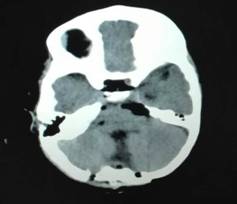

从开始麻醉到手术结束仅仅用了两个半小时的时间,出血仅100ml。手术结束后患儿转入ICU。“手术过程顺利,肿瘤组织被完全切除,脑脊液的循环通路打开了,应该会有一个不错的结果”,单峤主任第一时间向患儿的父母报告了这个好消息。

术后:肿瘤完全切除